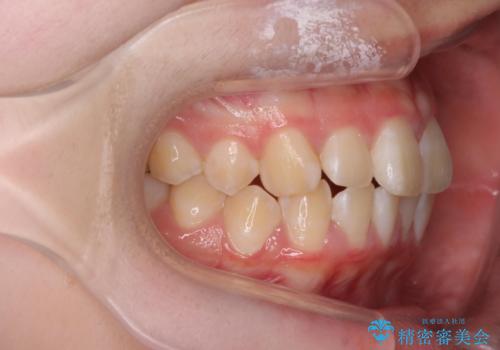

前歯のがたつき気になる。インビザラインモデレート

- 前歯のがたつきが気になるとの事で来院。

マウスピース矯正希望でしたのでインビザラインモデレートで治療を行いました。

がたつきが無くなり満足して頂けました。